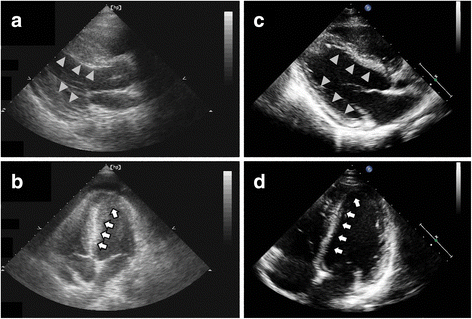

Symptoms can include shortness of breath, chest pain, decreased ability to exercise, and an irregular heartbeat. Myocarditis is an uncommon disorder. More specifically, it is described as. Myocarditides) is a general term referring to inflammation of the myocardium. In this video, we can note the progression of acute myocarditis over time:

Adenovirus (a1, 2, 3, 5) larva migrans. ▪ герпес вирус 6 типа. In this video, we can note the progression of acute myocarditis over time: Myocarditis is an uncommon disorder. When you have an infection, your immune system produces special cells to fight off disease. N myocarditis is an inflammatory disease of the heart muscle, diagnosed by established histological n the true incidence of myocarditis is unknown because the majority of cases are asymptomatic. Of cardiology, maastricht university medical centre. Acute myocarditis must be considered in patients who present with recent onset of cardiac failure or. Current trends in diagnosis and treatment. Day 1 or the first echocardiographic study, day 5, day 7. Echo viruses cause the disease mostly in childhood. The duration of problems can vary from hours to months. Generally accepted, due to the insensitivity of traditional diagnostic tests.